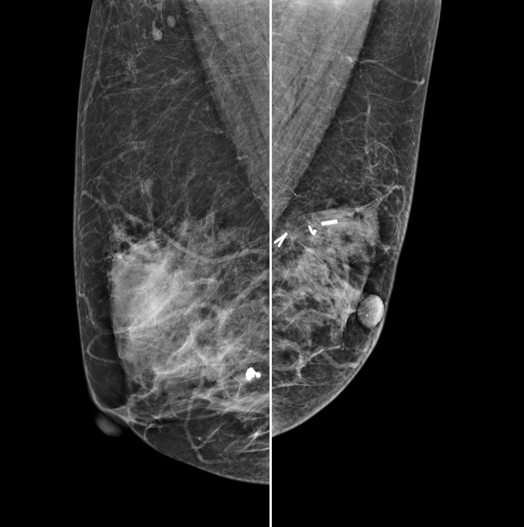

The X-ray tube moves on the breast and takes high-definition, high-resolution images with high contrast from various angles.

The images are reconstructed in 3D to provide accurate information about the location and condition of the lesion.

HESTIA supports "Synthetic 2D" that generates 2D images only by tomography shooting without additional 2D shooting.